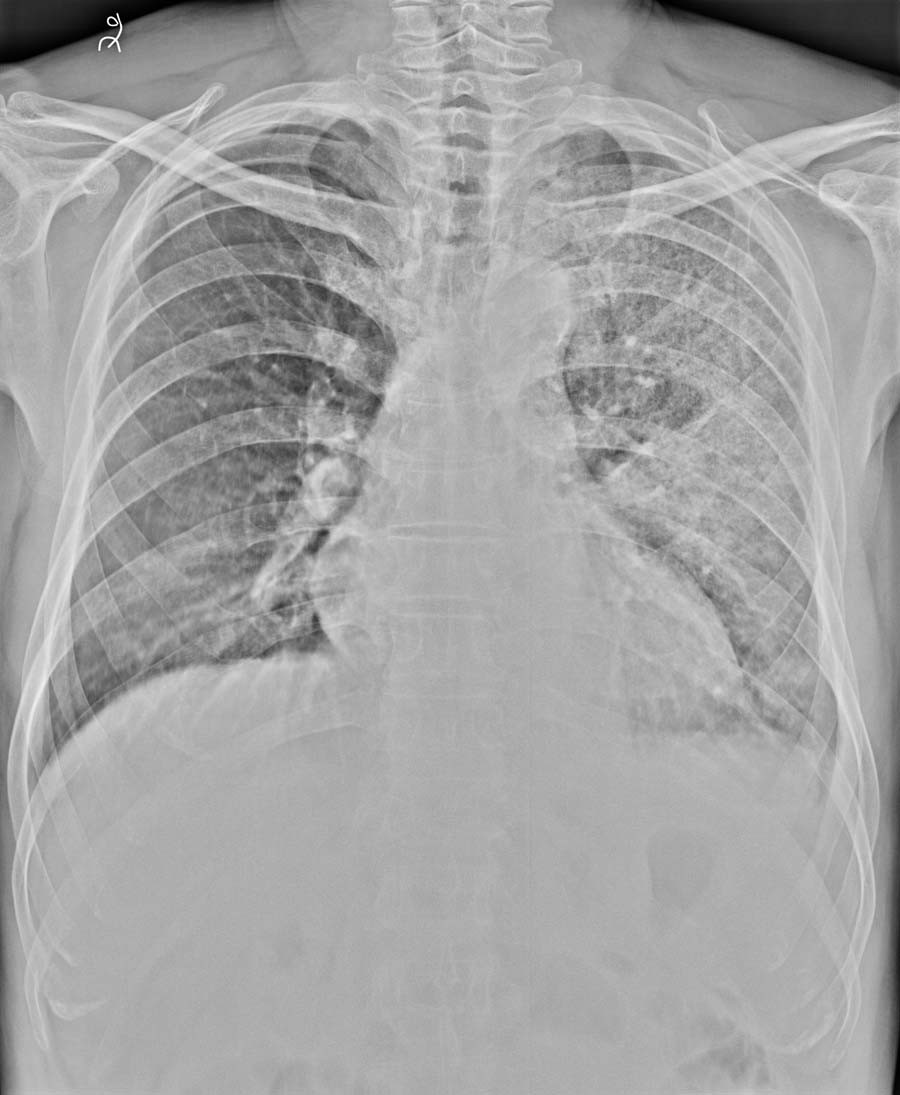

标题: X2594:男,56岁,左肺阴影性质?

男,56岁,咯血2天,左肺阴影性质?

左肺散在小结节状,片状高密度影,边缘模糊,以背段为重,肺门散在点状钙化影。考虑结核?建议ct建查。

有炎性病变是肯定的,上肺有小颗粒状阴影及条索状影,不除外有结核可能,建议抗炎治疗一周后来复查。

左肺弥漫性病变,建议ct检查。

不能单纯感染吧,还是同意弥漫性病变为好,包括肺出血也是这种改变,当然出血的原因待查,做一ct吧

炎性病变,陈旧性肺结核,右下肺野也象有斑片影。

左肺感染,左侧胸腔积液

结核或肺泡癌可疑